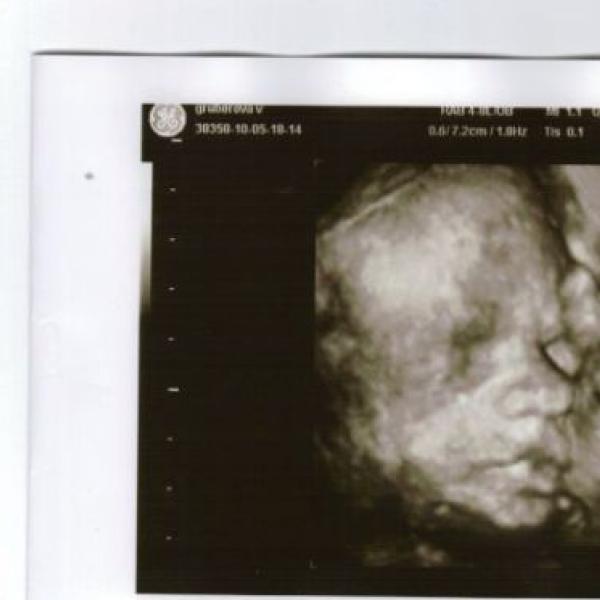

tak holky,dneska sme byli na kontrole...a vse je jak ma..jsem 30+4 a nahore mam 9 kilo.malej vazi 1300g a je hlavickou dolu.a zrovna zival kdyz ho dr.